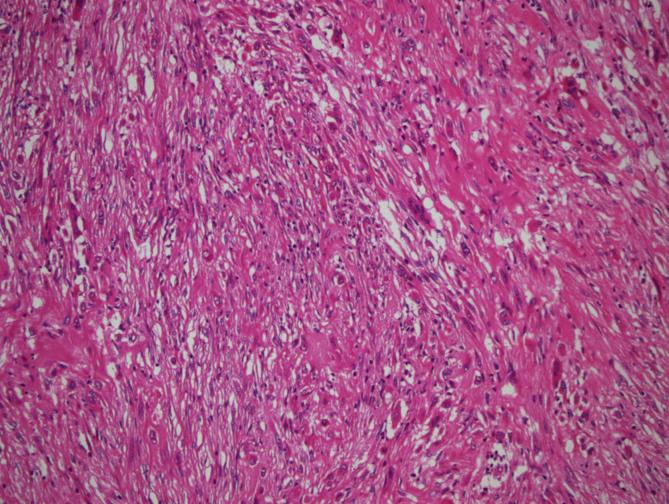

Tumors were localized most frequently at proximal tibia and distal femur, respectively. In 11 cases areas rich in fibrohistiocytic component and in 20 cases aneurysmal bone cyst like component were observed. In 2 cases both components were present. Twenty three cases recurred. In 1 case which was primarily located at calcaneus, tumor metastasized to lung 4 years later during follow-up.

GCT can be confused with other tumor or tumor-like lesions involving giant cells. Secondary changes such as fibrohistiocytic or aneurysmal bone cyst-like components and coagulation necrosis were frequently seen in conventional giant cell tumor of bone. For tumors having prominent fibrohistiocytic and/or aneurysmal bone cyst-like components, in order to detect characteristic areas representing GCT, additional sampling is essential. Although secondary histopathological changes do not appear to affect clinical outcome, these features are important in differential diagnosis. Approximately one fifth of GCT cases show recurrence and sacrum and foot bones were the most frequent sites for recurrence.

肿瘤最常分别位于胫骨近端和股骨远端。在11例中观察到富含纤维组织细胞成分的区域,20例中观察到动脉瘤样骨囊肿样成分。2例中两种成分均存在。23例复发。1例最初位于跟骨,随访4年后肿瘤转移至肺。

骨巨细胞瘤可能与其他涉及巨细胞的肿瘤或肿瘤样病变相混淆。在传统骨巨细胞瘤中,常见纤维组织细胞或动脉瘤样骨囊肿样成分以及凝固性坏死等继发性改变。对于具有显著纤维组织细胞和/或动脉瘤样骨囊肿样成分的肿瘤,为了检测代表骨巨细胞瘤的特征区域,额外取材至关重要。尽管继发性组织病理学改变似乎不影响临床结果,但这些特征在鉴别诊断中很重要。约五分之一的骨巨细胞瘤病例会复发,骶骨和足部骨骼是最常见的复发部位。